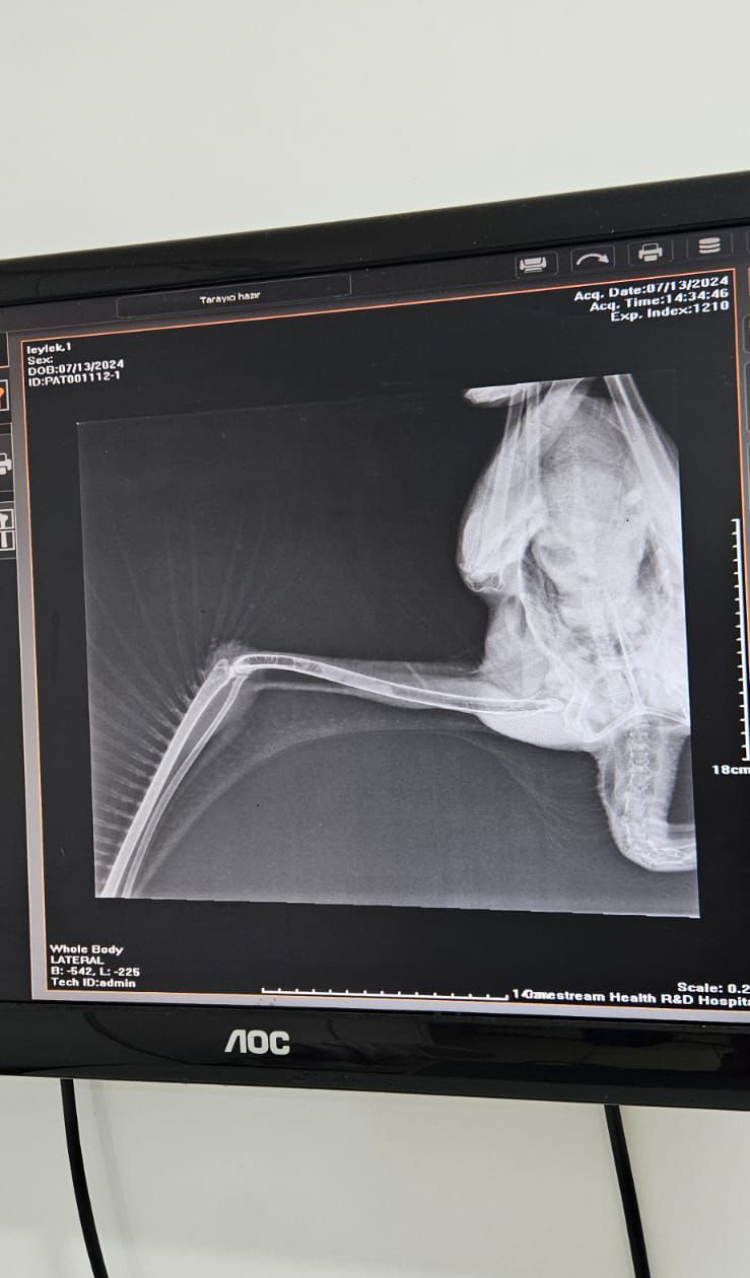

Ekipler, sağlık durumu hakkında detaylı bilgi sahibi olmak ve gerekli muayeneyi uygulamak adına yaralı leyleği Sahipsiz Hayvanlar Doğal Yaşam ve Tedavi Merkezi’ne götürdü. Veteriner hekim tarafından sağlık kontrolü yapılan ve röntgeni çekilen leyleğin, kanadında darbeye dayalı yaralanma olduğu ve bu yüzden uçamadığı tespit edildi. Yapılan medikal tedavinin ardında birkaç gün içerisinde sağlığına kavuşması beklenen leylek, Büyükşehir Belediyesi Hayvanat Bahçesi’ne teslim edildi.